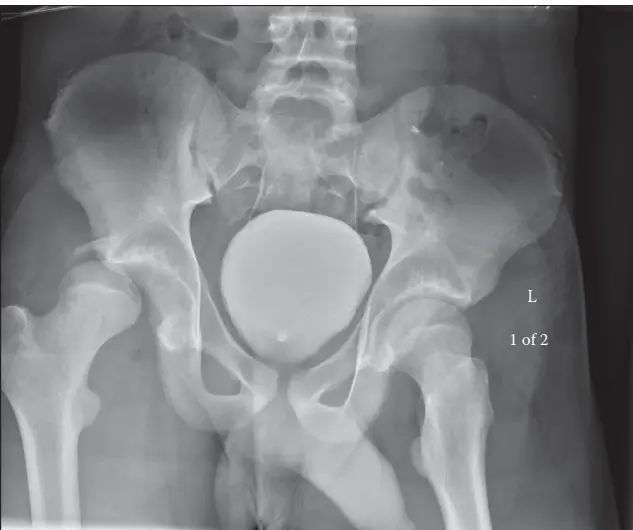

توضح الصور الإشعاعية أعلاه حالة الفصال العظمي في مفصل الورك الأيسر للمريض.

تُظهر هذه الصور الإشعاعية تآكل الغضاريف وتغيرات في بنية العظام، مما يؤكد تشخيص الفصال العظمي.